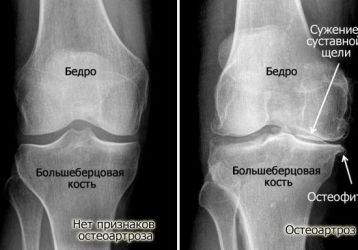

Артроз — это одно из самых опасных поражений сочленений, которое без надлежащей терапии может привести к деформации, а также дисфункции сочленений. Болезнь имеет дегенеративно-дистрофический характер. В основном поражается именно хрящевая ткань, которая отвечает за амортизационные свойства суставов.

Характеризуется патология сильными болевыми ощущениями, ограничением подвижности человека, а также изменением самого сочленения (часто не обратимым). Существуют такие виды заболевания:

• Остеоартроз. Это хроническая прогрессирующая патология синовиальной части костного соединения. Она бывает генерализированной и локализованной.